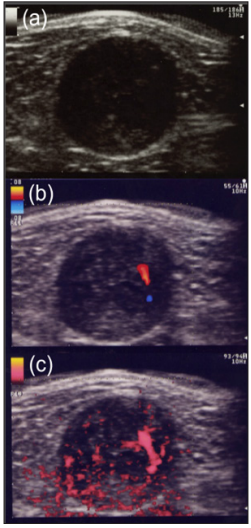

Figure 1: Schwannoma pathologically confirmed in the thigh in a 47-year-old male.

a) On gray-scale US show a well-defined hypoechoic nodule with cystic change and eccentric nerve-tumor position.

b) A few central blood flow signals are depicted on color Doppler US.

c) Power Doppler US show many central vascularity in a mass.

Neurilemmomas or Schwannoma: Neurilemmoma, or schwannomas, occur along the course of a peripheral nerve. They may be tender and firm and have a flash- to pale-pink color. Histologically, S-shaped nuclei, Vero cay bodies are characteristic. Both Antoni A and Antoni B tissue may be present. The nervetumor association and vascularity of the tumors could be useful for differentiation of between schwannoma and neuroma. Schwannoma shows eccentric nerve-tumor position on gray-scale US and vascularity within the tumor on color Doppler US [12]. Tsai et al. reported that color Doppler US shows hyper vascular flow signals in a patient with schwannoma [21]. US findings of pathologically confirmed as a schwannoma in the thigh in a 47-year-old male were present as follows: A well-defined hypoechoic nodule with cystic change and eccentric nerve-tumor position were depicted on grayscale US. Blood flow signals were more detectable on power Doppler US than on color Doppler US (Figure 1a-1c). Photomicrograph shows well-defined ovoid mass with degenerative cystic foci. Less cellular Antony type B area consisting of neuronal spindle cells forming Vero cay bodies was detected (Figure 2a- 2c). Tumors were comprehensively diagnosed as schwannomas in the upper extremity in a 46-year-old female were noted as follows: The tumor presents as well-defined hypoechoic nodule without an obviously nerve-tumor position on gray-scale US. Many central blood flow signals were depicted both on color Doppler US and power Doppler US (Figure 3a-3c). Figure 4 shows magnetic resonance angiography image as vascular tumors, suggesting schwannomas. ALM mimic schwannoma very closely. The features of nerve-tumor association and adjacent vessel could be useful for differentiation of between schwannoma and ALM as previously described [7].